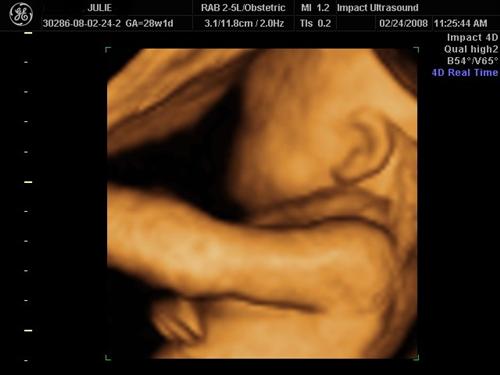

Cord around his neck I am bringing this to my next midwife appt!

Again, notice the cord